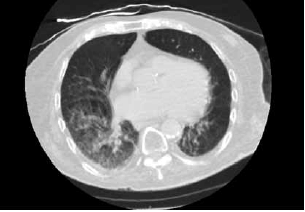

Paciente de 90 anos e admitido no Pronto-socorro com queixa de tosse, sonolência e diminuição da ingestão alimentar. Foi realizada uma tomografia computadorizada de tórax mostrada a seguir.

(Arquivo pessoal; imagem usada com autorização)